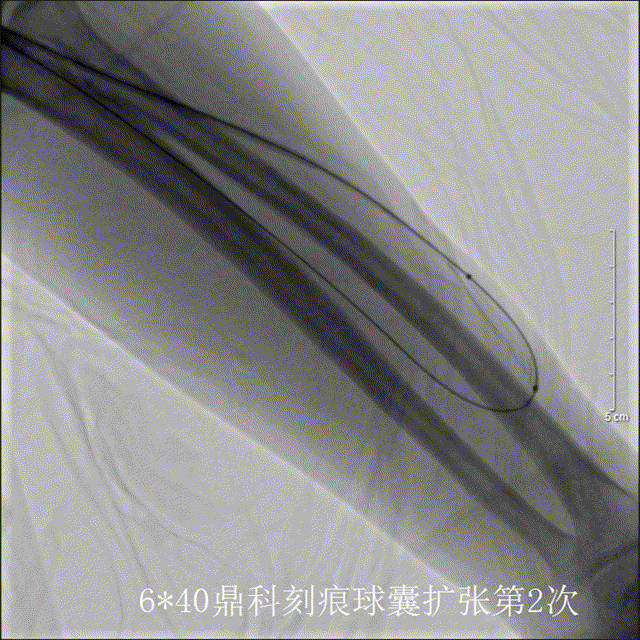

应用6*40mm高压刻痕球囊第2次扩张见狭窄段完全扩开

鼎科高压刻痕球囊扩张后造影见内瘘血流非常满意